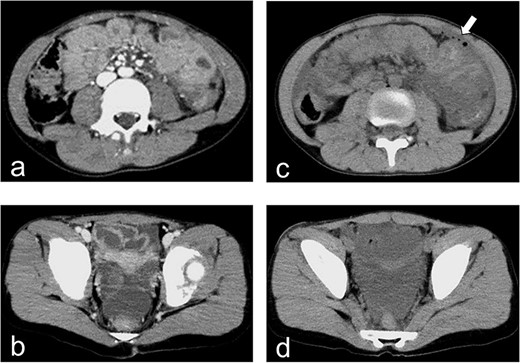

Enhanced and plain CT. (a) Enhanced CT on hospital day 1 demonstrates the absence of free air. (b) Enhanced CT on hospital day 1 demonstrates the presence of a fluid collection in the pelvic cavity. (c) Plain CT demonstrates free air in the left abdominal cavity. (d) Plain CT demonstrates a significant amount of fluid in the pelvic cavity.

A 10-year-old girl was sitting in the back seat of a right-hand drive car, behind the driver, when another car came from the front and bumped into the patient’s car on the right side. The patient was restrained in a three-point seat belt (shoulder and lap belts). She was transferred to our hospital, where she was alert and communicative on arrival. Her chief complaint was abdominal pain. She was 137-cm tall and weighed 30 kg. On presentation, her heart rate was 87 beats/min, her blood pressure was 123/62 mm Hg, her respiratory rate was 20 breaths per minute, her oxygen saturation was 100% and her temperature was 36.7°C. A seat belt sign was observed, with contusions on the forehead and the right iliac region. Her abdomen was tender and she displayed guarding. Focused assessment with ultrasonography for trauma showed a fluid collection in the pelvic cavity. Enhanced computed tomography (CT) demonstrated no free air but confirmed the presence of a fluid collection in the pelvic cavity (Fig. 1a and b). Radiography and CT showed a fracture of the lumbar spine at L3 (Fig. 2a–c).

The patient was admitted for observation and followed carefully for suspected intestinal injury. The following day, she was tachycardic and febrile, and her abdomen was tender with guarding. Her C-reactive protein level increased from 0.08 mg/dL on the day of admission to 6.92 mg/dL on hospital day 2 (Table 1), while her serum amylase level increased from 132 to 319 IU/L (Table 1). Plain CT demonstrated free air in the left abdominal cavity and a significant fluid collection in the pelvic cavity (Fig. 1c and d). We diagnosed an intestinal injury and performed exploratory laparoscopic surgery.